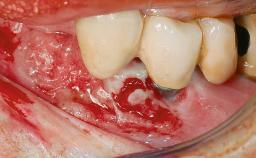

This case describes the ongoing management of a 64-year-old healthy, non-smoking female patient with erosive oral lichen planus (OLP) affecting the gingivae and the buccal and lingual mucosa. The peri-implant mucosa was also affected subsequent to implant placement. The patient had osseointegrated implants (four in the maxilla, four in the mandible) placed following extraction of hopeless teeth and a healing period. The patient had a history of OLP prior to implant placement and had been referred to an oral-medicine specialist for definitive diagnosis and treatment. She exhibited generalized oral mucosal involvement. Following a clinical assessment, biopsy, and blood tests, she was treated with topical corticosteroids. Systemic prednisolone was reserved for severe flare-ups. Amphotericin lozenges were used in combination with corticosteroid treatment to prevent the development of oral candidiasis.